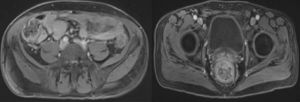

入侵門戶不明部分病例發病前與昆蟲叮咬有關,可能是節肢動物作傳播媒介。感染為逐漸增大的皮下結節皮下結節較堅硬邊界清楚局限,觸摸可活動,表面皮膚萎縮伴色素減退或色素增加,不發生潰瘍,偶爾可與下方皮膚粘連但不與肌肉筋膜粘連,結節可腫大累及整個肩部、臂部軀幹上部、面、頸及整個腿部和臀部,個別病例可累及肝、腸等內臟器官及肌肉。

感染為逐漸增大的皮下結節,入侵門戶不明,部分病例發病前與昆蟲叮咬有關,可能是節肢動物作傳播媒介。皮下結節較堅硬邊界清楚局限觸摸可活動,表麵皮膚萎縮,伴色素減退或色素增加,不發生潰瘍,偶爾可與下方皮膚粘連但不與肌肉筋膜粘連,結節可腫大累及整個肩部、臂部、軀幹上部、面、頸及整個腿部和臀部,個別病例可累及肝、腸等內臟器官及肌肉。局部淋巴結不受累未發現經血液、淋巴管播散的報導。病人可有發熱,白細胞計數增多。